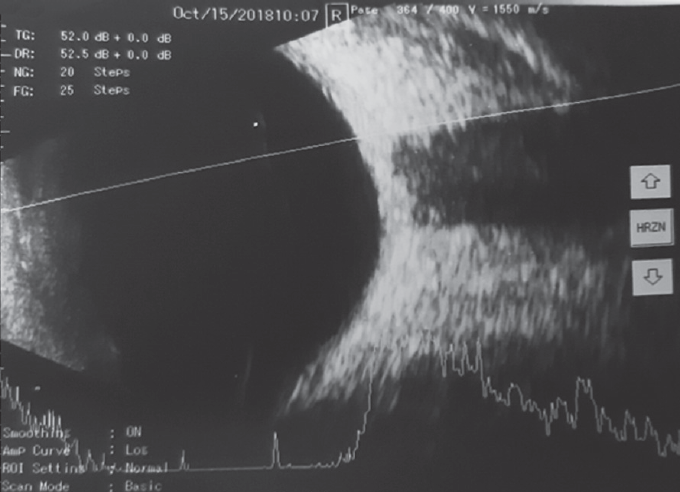

Рис. 5. A- и B-сканирование пациентки Р. при первичном обращении. В-скан: аксиальная горизонтальная проекция, умеренное количество помутнений в стекловидном теле. А-скан: 6 пиков средней и низкой эхогенности

Fig. 5. Initial treatment, Patient R.: B-scan: maximum horizontal projection, moderate amount of “clouding” in the vitreous body. A-scan: 6 peaks of medium and low echogenicity